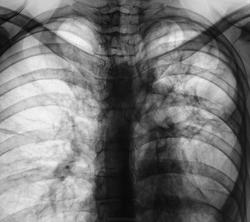

Через пол года после выписки из облтуббольницы.

Через год плановое исследование.